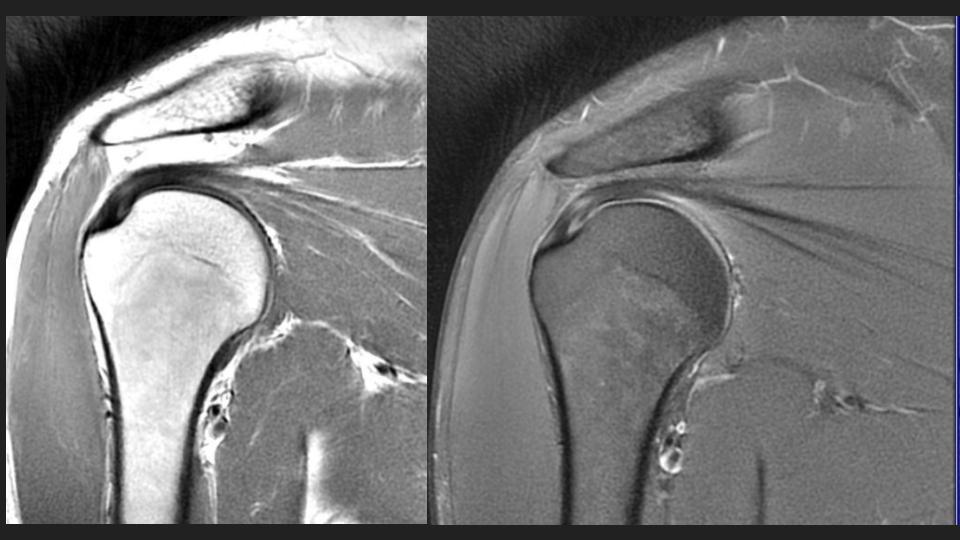

36M with chronic pain and limited motion 3 years after work related injury

My colleague had to share this with me after a failed attempt at arthrography. He puts the shoulder in Grashey, but it doesnt really look like Grashey. No matter what, he couldnt get in and converted it to a routine MRI. The first set of Cor images look so nice....or do they? The crazy thing is that the injury was 3 years ago. Not all workers comp is bogus. I was taught the posterior shoulder dislocation locks the shoulder in internal rotation, but based on the axial image, it is not. 1) Why is that? 2) I think thats partly why the scout image for the arthrogram was so misleading.

dislocation ( RID4770 )